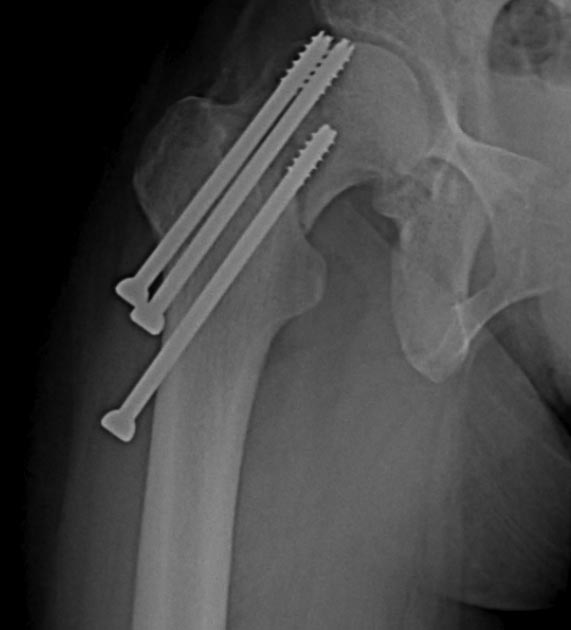

Доброго времени суток. За правый (с винтами) надо бороться. Вальгизирующая остеотомия позволит и перелом срастить и скомпрометированный участок головки выведет из под нагрузки. А вот с другой стороны (с гвоздем) перспективы сохранения головки сомнительные, тем более на таком сроке. Головка резко порозная. Тут можно дождаться консолидации диафиза и протезировать потом чем угодно.

А почему такой пессимизм справа? Мне как-то кажется что там прихватилось, по крайней мере имеющиеся снимки в обратном не убеждают. Надо бы их повторить и тогда уж решать..

простой вальгизацией здесь не обойтись, малый вертел полностью виден, те ротация не менее 30 град, плюс аксиальное смещение, на какую площадь контакта можно рассчитывать? Максимум до 20% за счет внедрения задней стенки шейки в головку.

На шейке с шурупами понятно остеотомия и фиксатор с угловой стабильностью, а слева надо бы определится что с головкой